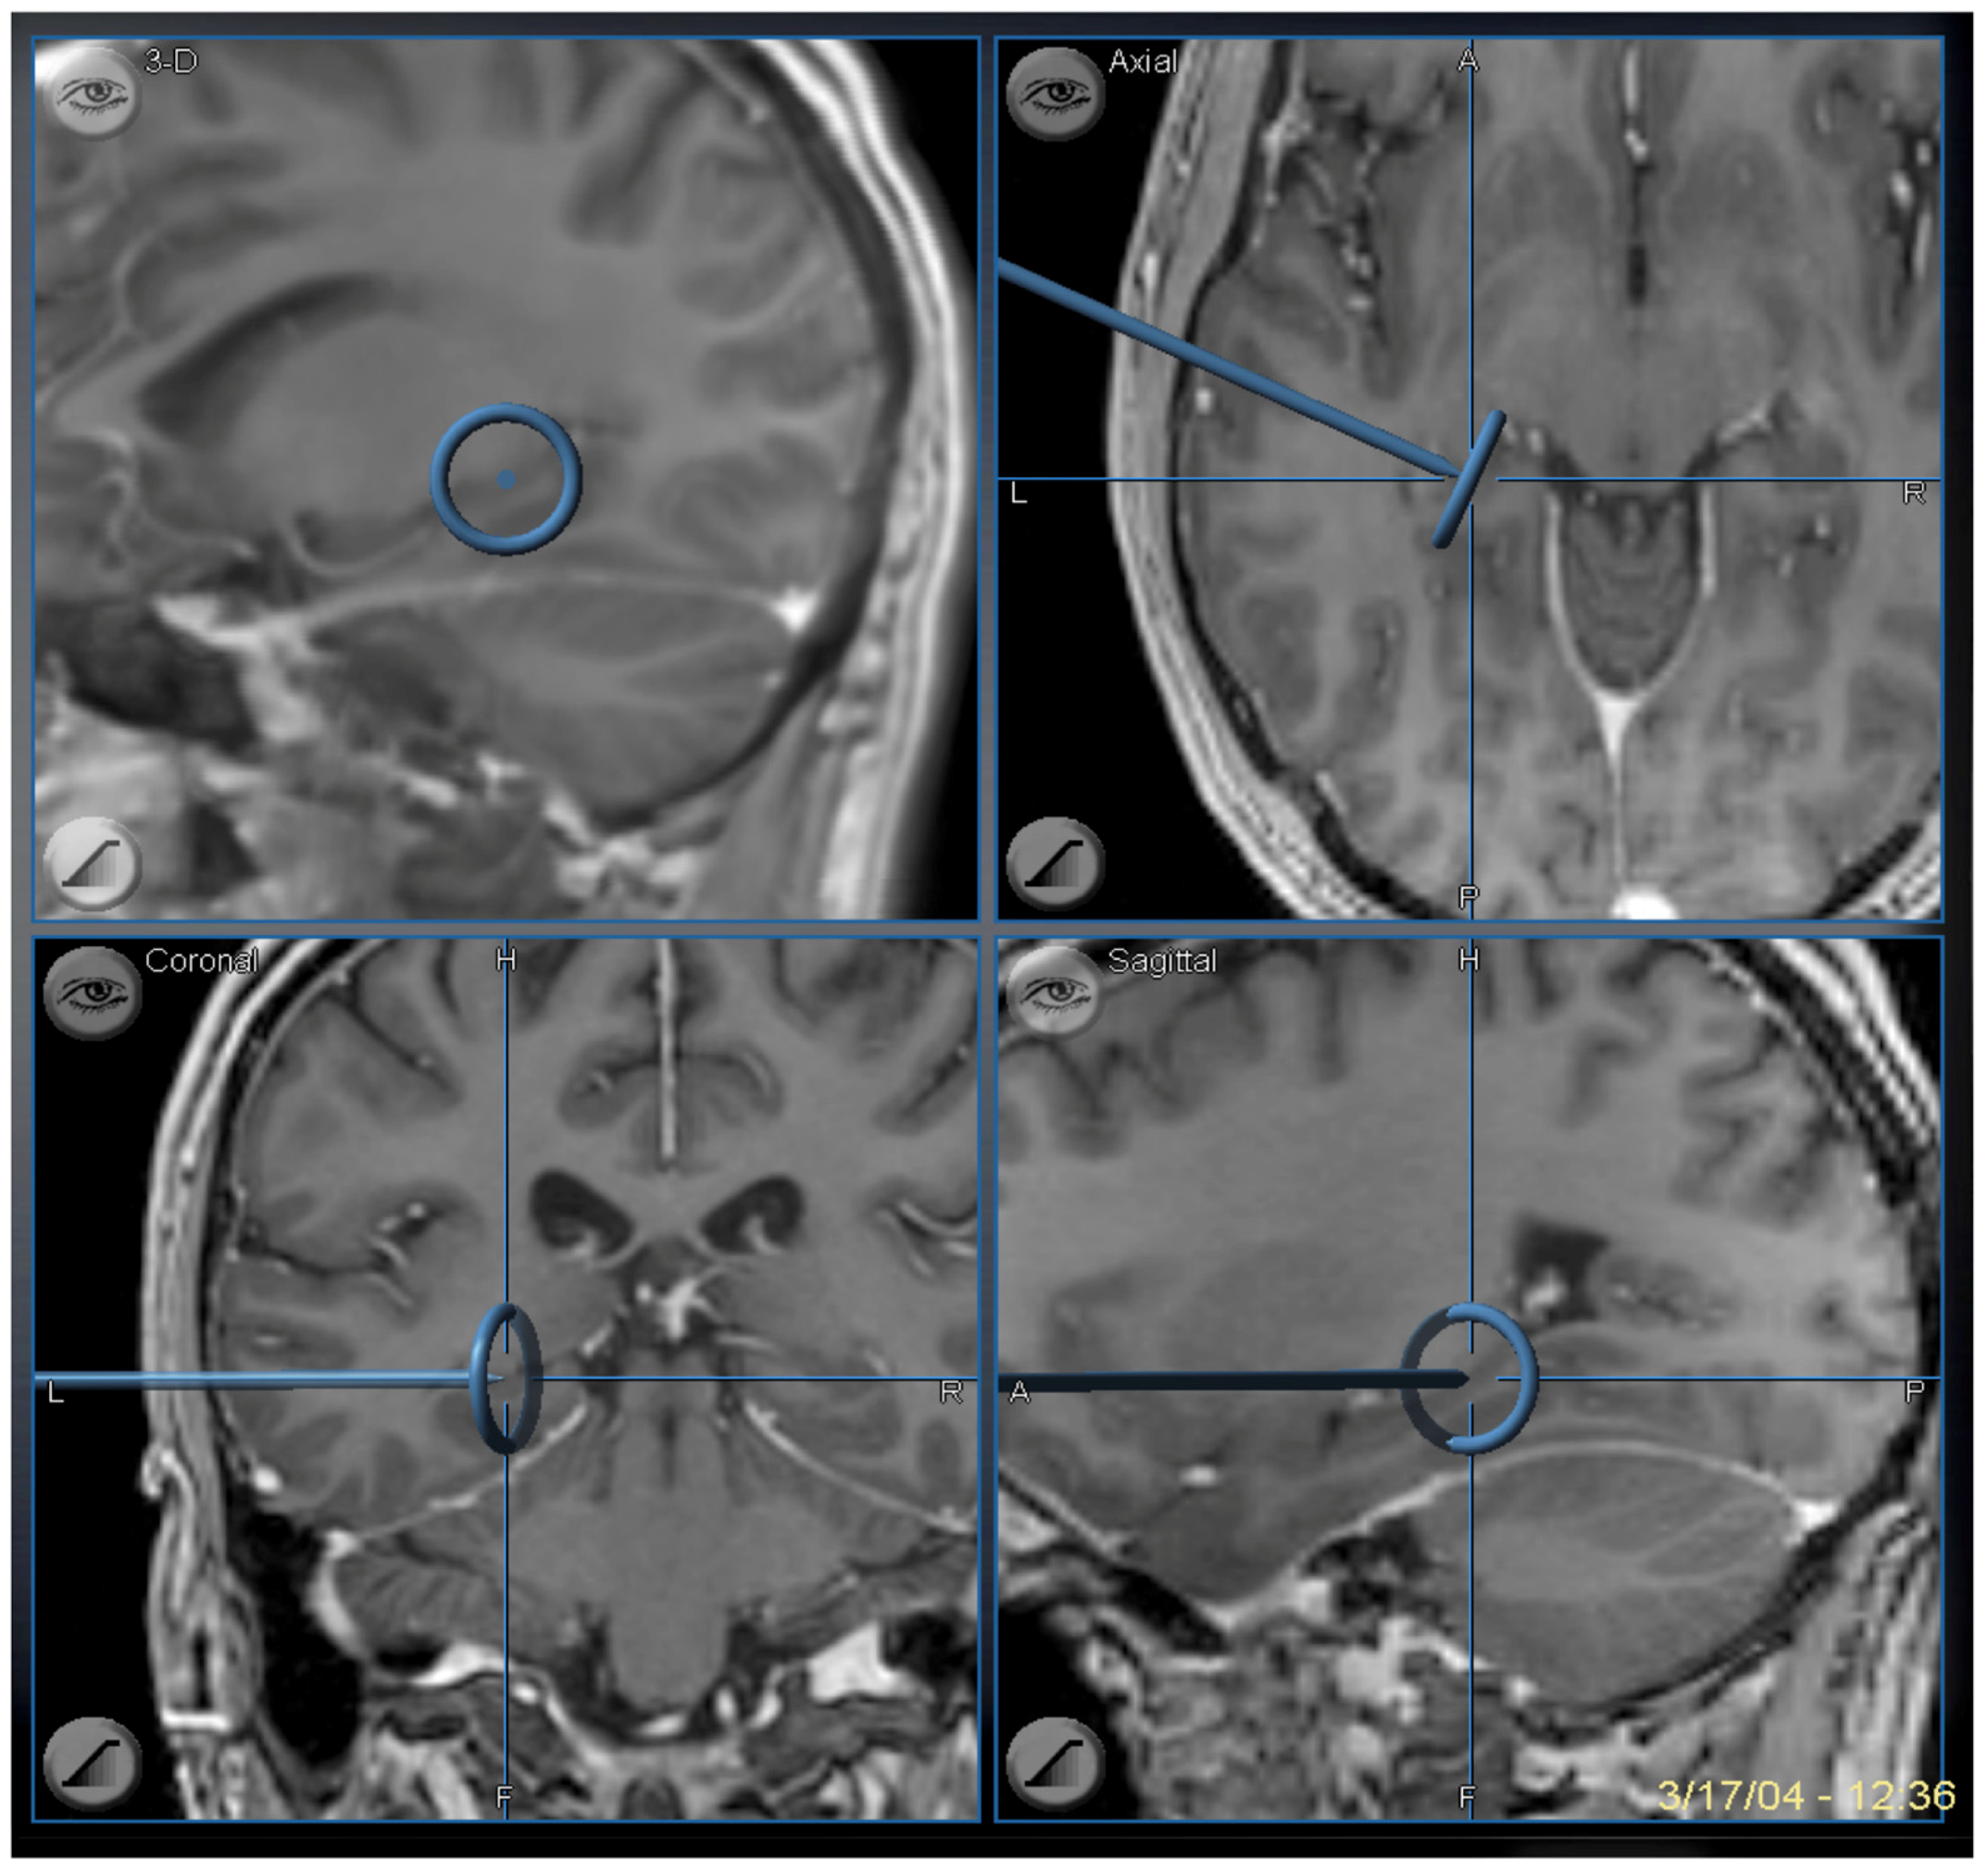

The completion of the SAH corresponds to removal of the mesial temporal structures found between the choroid plexus and collateral sulcus that includes the uncus, amygdala, hippocampus, parahippocampus, and fimbria. All of which are removed by keeping the underlying pia intact. The anterior limit is to the anterior extent of the uncus at the tentorial incisura and the posterior limit is back to the level of the midbrain tectum (Figure 9).

Figure 9. Image guidance view of the navigation pointer at the posterior extent of the hippocampal removal, which corresponds to the level of the midbrain tectum.